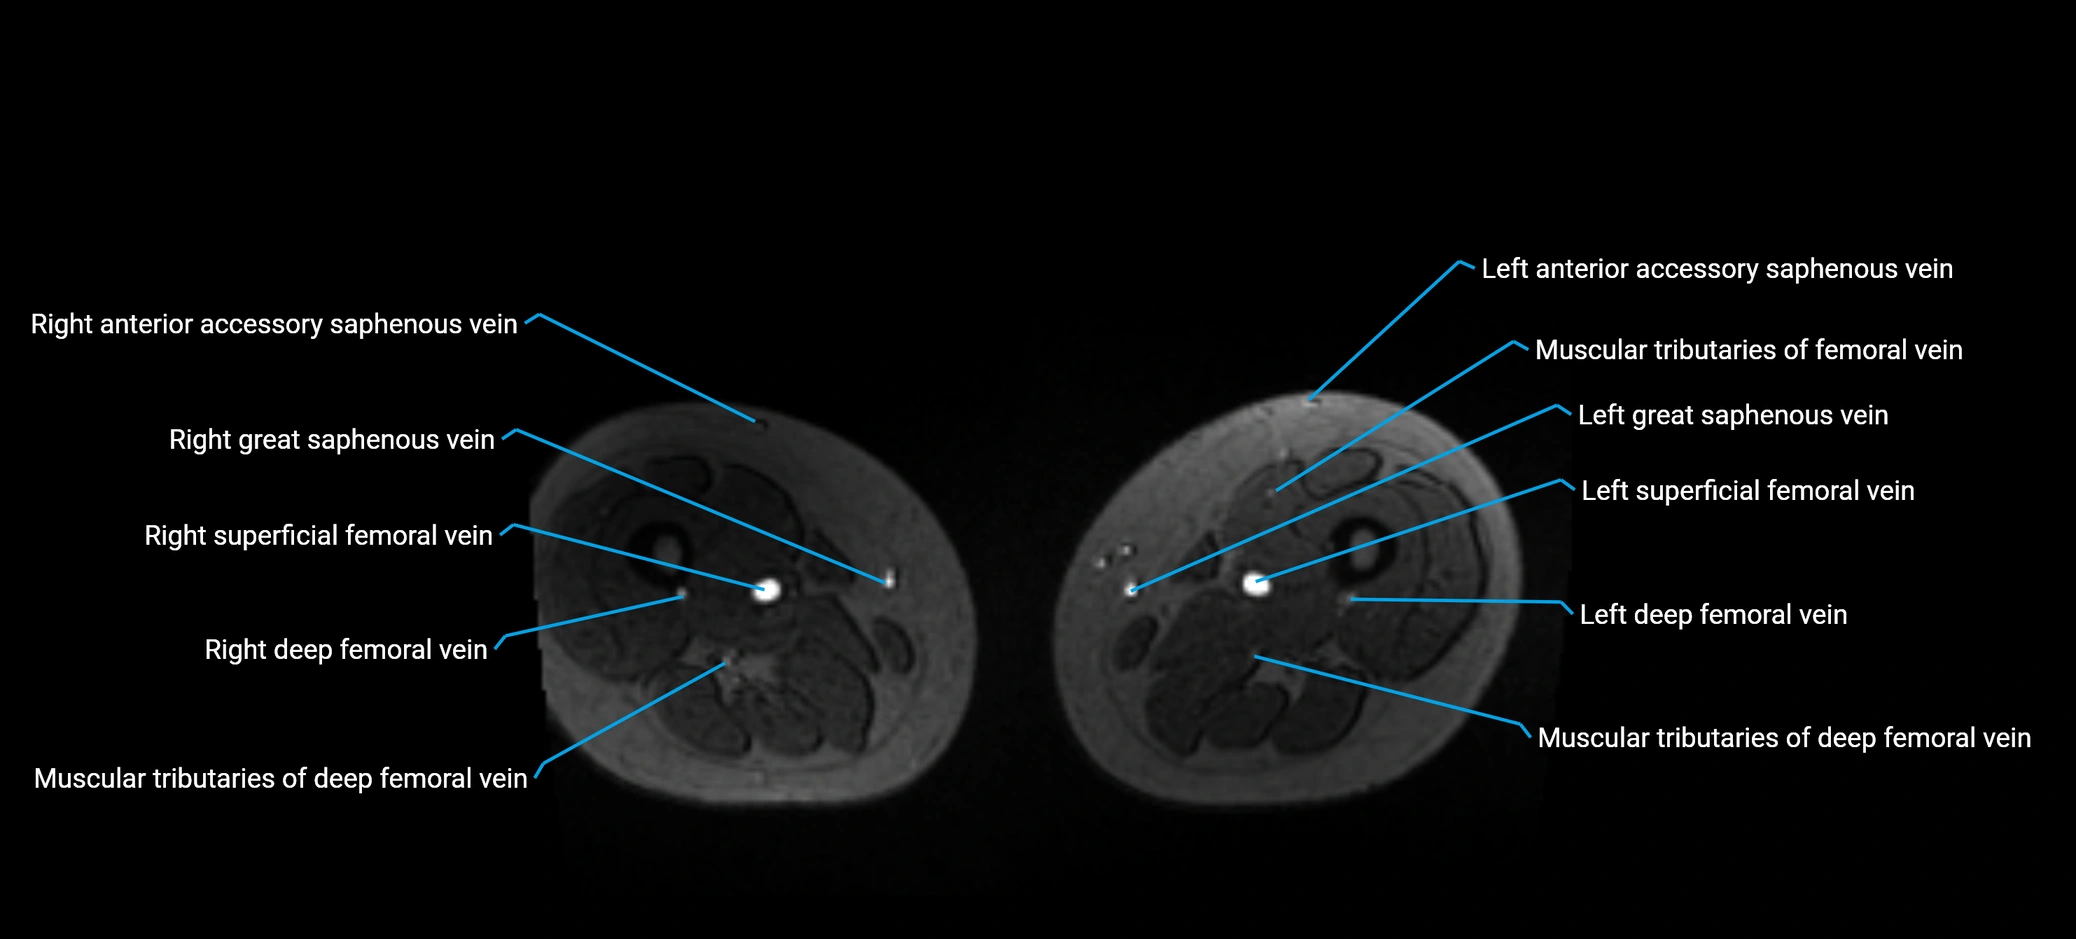

MRI image

image